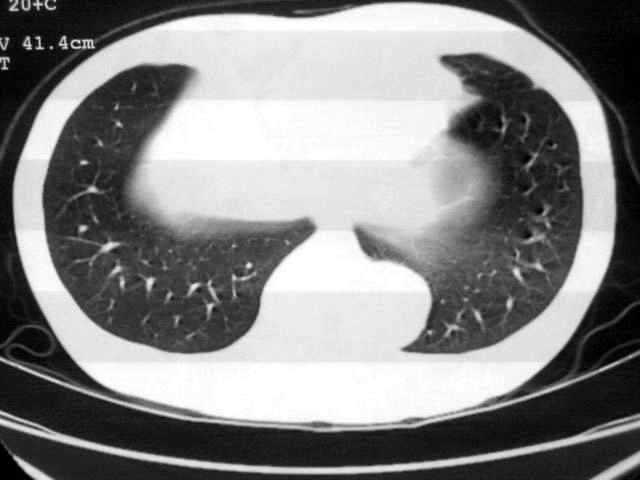

以下是引用苯小孩在2007-4-24 19:46:00的发言:[br]左下肺内侧基底段,见类圆形病灶,边缘清晰光滑.强化后轻中度强化.<平扫第4层面似有从腹主动脉相连血管影,可惜强化扫描这层没有抓住>考虑:左下肺隔离症.建议dsa或薄层强化重建观察.

以下是引用同在2007-4-24 20:11:00的发言:[br]考虑肺隔离症